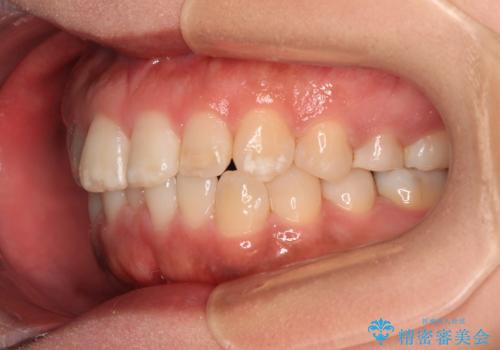

- 上下前歯の叢生を気にして来院された患者様です。

軽度な叢生であり、安価で短期間の治療を規模されていたため、インビザライン・モデレートを用いて矯正治療を行うこととしました。

インビザライン・モデレートは、製作できるアライナーの枚数に制限があるため、移動可能な量に限りがあるものの、インビザライン・ライトよりも枚数が多いため、幅広い症例に対応可能です。